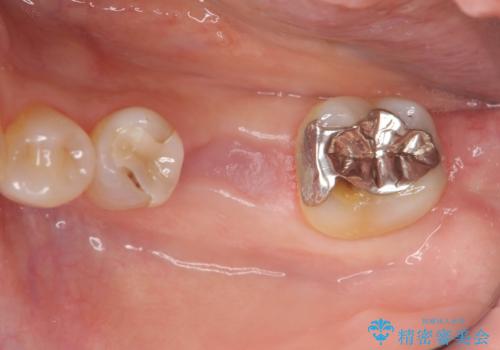

前後の歯も一緒に審美性を回復することができ、喜んでいただくことができました。

ブリッジは早期に審美性・機能性を回復できる治療法です。